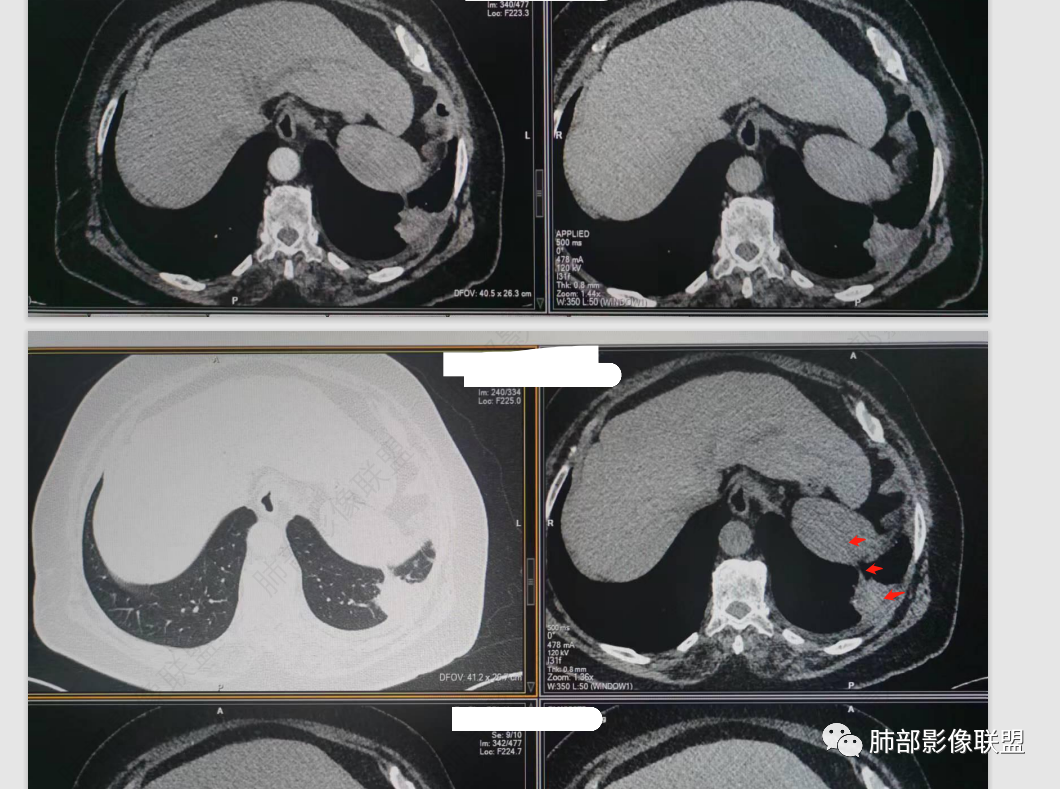

秦化君:左肺下叶外基底段胸膜下软组织密度结节性,边缘毛糙与血管相连,密度不均,增强后病灶内边界不清低密度区,胸膜栽桩,少量胸腔积液。考虑恶性病变,腺癌可能。真菌待排。

谢加平:老年女性,慢性咳嗽,咳白痰史,左肺下叶后基底段胸膜下肿块,类圆形,边界清膨隆,密度不均匀,低强化及小灶性坏死,坏死轮廊不清,胸膜下栽赃明显,左侧胸腔少量积液,向胸壁肌侵犯,另肿块近心侧见支指套征,粘液低密度,支持恶性,粘液腺Ca,经皮肺穿刺活检明确诊断。

361度:老年女性,发热,胸部CT示左下肺胸膜下结节影,血管集束,毛棘,密度不均,胸膜栽赃,少量胸腔积液,不均匀强化,坏死边界不清,肿标轻微升高,考虑恶性,鳞癌合并感染。

红星:老年女性患者。胸膜下结节病变,明显的膨胀,并局部侵犯胸膜,增强明显的强化。病灶周围带有局灶的渗出性改变以及条索上的影。考虑腺癌的可能性大,鉴别结核肉芽肿性病变。

春秋:左肺下叶胸膜下结节,边缘平直,内见低密度区,胸膜下胸腔积液相隔,考虑炎性结节可能性大,伴小脓肿形成。

宇宙:左肺下叶胸膜下球形肿块,边界尚清,局部平直,局部膨隆,内侧缘长索条,胸膜栽赃,轻度不均匀强化,其内坏死边界欠清,左侧胸水,考虑腺癌,鉴别放线菌。

党医生:左下肺结节,整体呈不完全规则、局部呈球形结节,有较长、轻大的条索壮改变,球形病变区域与胸膜呈宽基底,密度不均匀、有液化低密度区,不均匀强化,总体分析考虑:结核可能大,其次炎性假瘤,肺癌可能小。

摘星空竹子:左肺下叶后基底段与外基底段交界处胸膜下椭圆形软组织肿块,边界尚清,密度欠均匀,患侧少量胸腔积液,增强扫描轻度或无强化,肿块中央可见斑片状低密度区,边界尚清,考虑OP伴脓肿或结核,鉴别腺癌。

李庆东:左肺下叶外基底段胸膜下球形软组织密度,边缘毛糙与血管相连,轻度强化,增强后病灶内边界不清低密度区,宽基底于胸膜,少量胸腔积液。考虑良性病变,炎性假瘤可能大。特殊感染待排,鉴别腺癌。

袁媛:左肺下叶胸膜下球形肿块,宽基底连于胸膜下,胸膜栽赃,边缘膨隆,有血管供应,增强有强化,考虑腺癌。

gaoql:倾向肿瘤,胸膜下脂肪间隙受累,有细角和nse升高,如果男性,要考虑鳞癌,但是个女性,还是先考虑腺癌的可能。感染指标升高,还需鉴别炎性肉芽肿性病变,能累及胸膜下间隙的,要鉴别脓肿或放线菌。

看图说话:胸膜下肿块,密度不均,边缘毛糙,增强后不均匀强化,胸膜栽赃,左侧胸腔积液,腺癌,鉴别肉芽肿。

songml:老年女性,反复咳嗽咳痰胸闷4年,加重伴发热一周。左肺下叶后基底段胸膜下肿块影,密度较均匀,边缘较清,侵及胸膜下脂肪间隙。考虑恶性病变,腺癌可能,鉴别真菌感染。

人生海海:左肺下叶不规则形软组织密度影,膨隆生长,边缘清楚,分叶,棘突征,支气管截断,血管纠集,病灶轻度强化、内多发坏死,左侧少量胸腔积液,考虑粘液腺癌,鉴别肺脓肿。

位移:老年女性,左肺下叶肺胸膜下团块影,边界清、毛糙,膨隆,内密度不均,不均匀强化,内见坏死,胸膜栽赃,胸腔少量积液,首先考虑恶性肿瘤,低分化腺癌,鉴别小细胞癌,炎性假瘤。

赖晓宇:膨隆,浅分叶,支气管截断,内部坏死边界不清,胸膜受累,胸腔积液,考虑恶性。

南边:今天的病例肺内部分基本都是炎性特点,问题就在于胸膜。

糊墙:肺内病灶不侵犯壁层胸膜或以外,与壁层胸膜相对而言分界清楚。

栽赃:病灶侵入壁层胸膜及胸膜外脂肪间隙、胸壁其他结构等,相对在病灶中央区域,与胸膜分界不清。

南边:看肺内病灶与胸膜分界清,增强后强化不一致,需要综合分析。

这是糊墙。

这就栽赃。都突到外面去了。